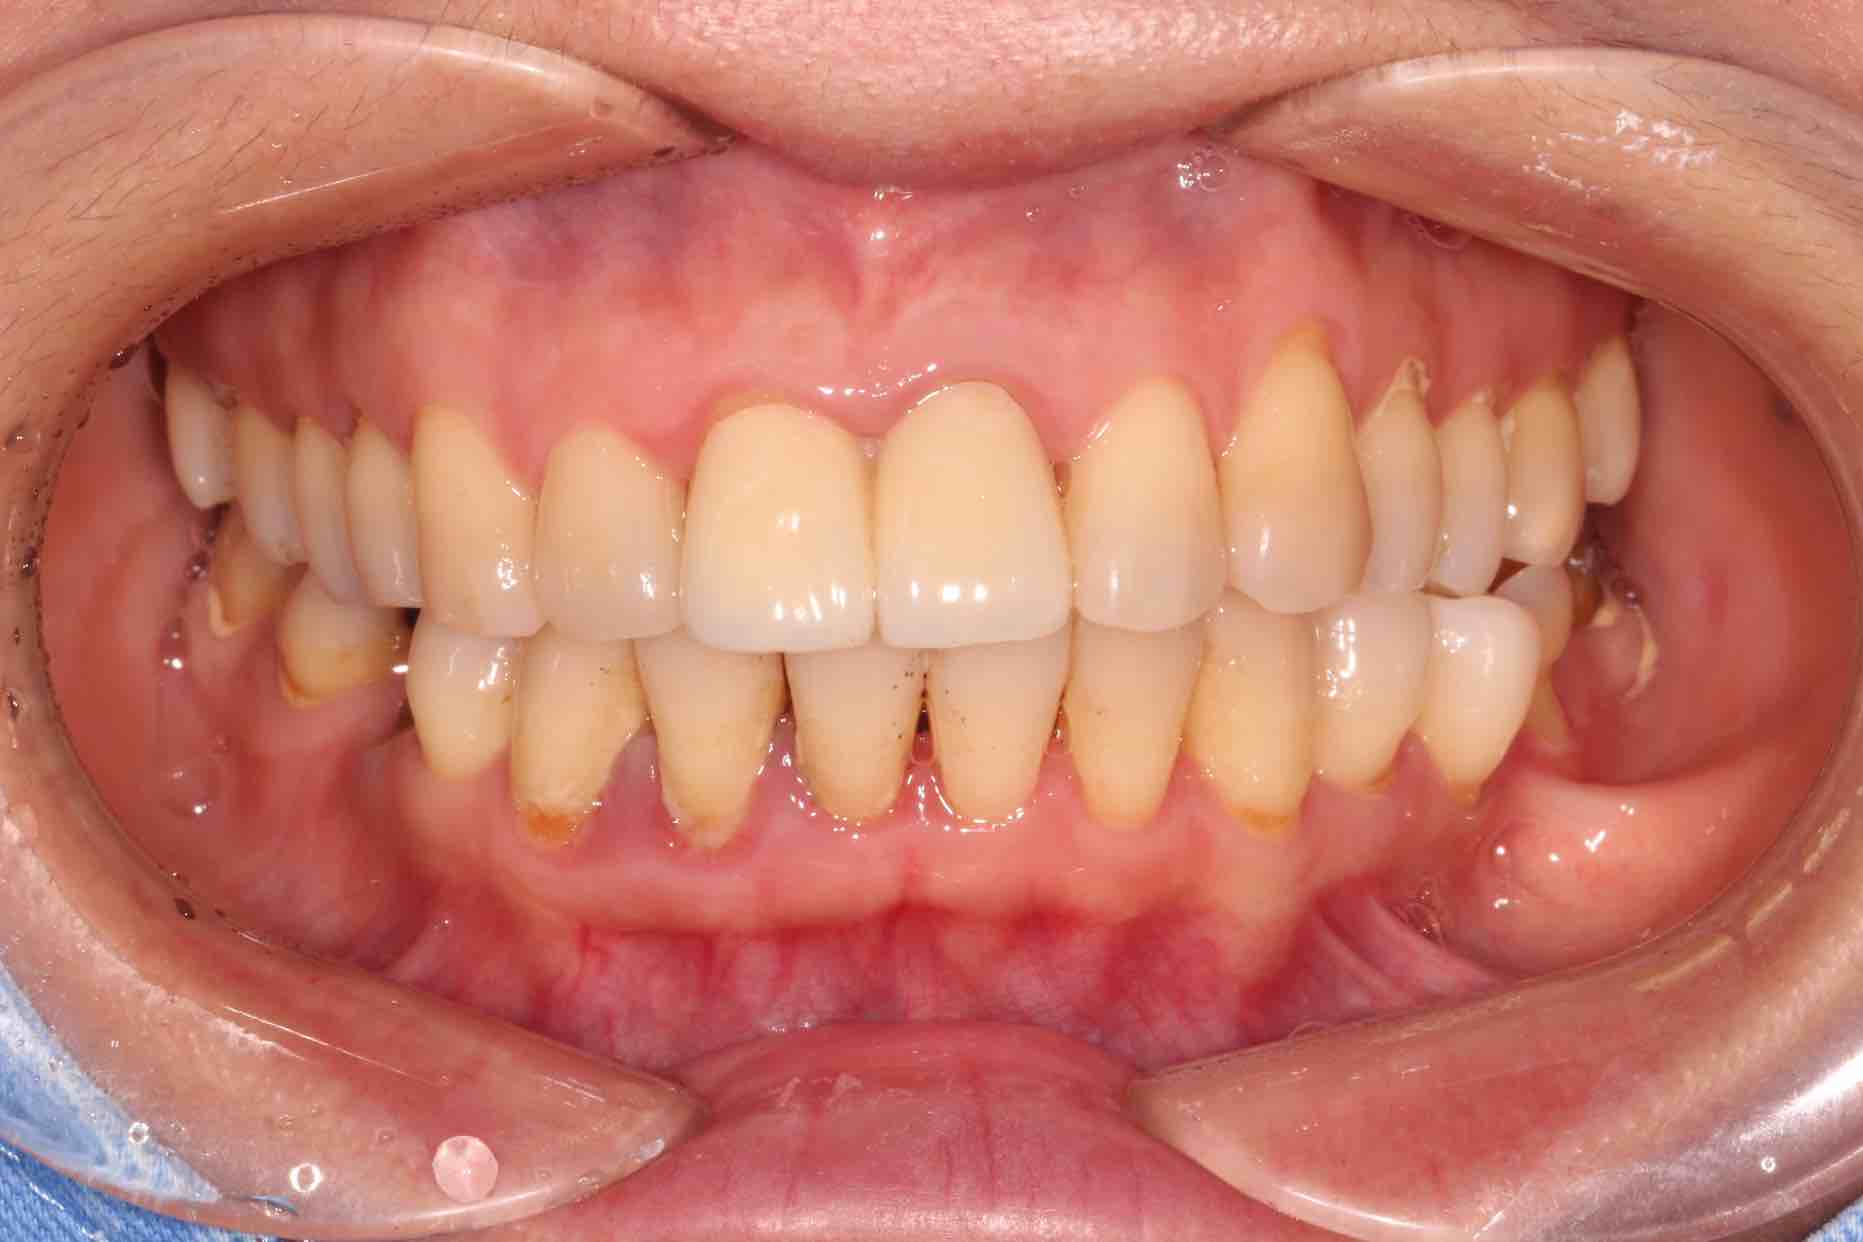

患者中年女性,11、21外院制作烤瓷冠,冠边缘不密合,牙龈退缩发黑,龈缘红肿,颜色不美观且X线检查21根管治疗不完善,由于牙冠不密合,11严重龋坏已有牙髓炎症状,我们对11进行了根管治疗,21进行了根管再治疗,最后CEREC扫描修复。